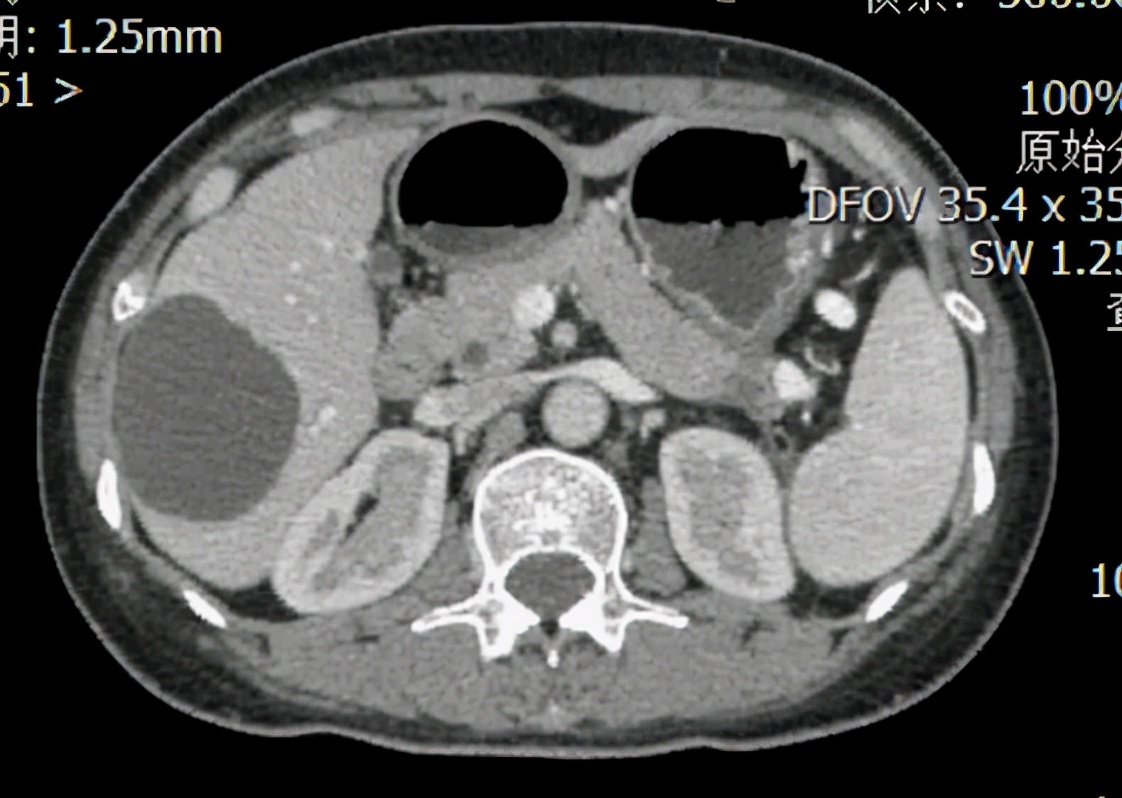

入院后完善相关影像学检查及病理会诊,再一次明确病理诊断及分期无误,切取肿瘤穿刺组织行基因检测,发现BRCA2体细胞突变,经多学科会诊,制定全身治疗方案为紫杉醇(白蛋白结合型)联合顺铂,经过10个周期规律化疗,复查影像学提示肝转移瘤、全身淋巴结转移瘤和腹膜转移瘤均已消失,胰腺原发灶较前明显缩小,直径约1cm。

图2:患者化疗9周期后的CT图,红框为胰腺尾部原发灶,直径约1cm。